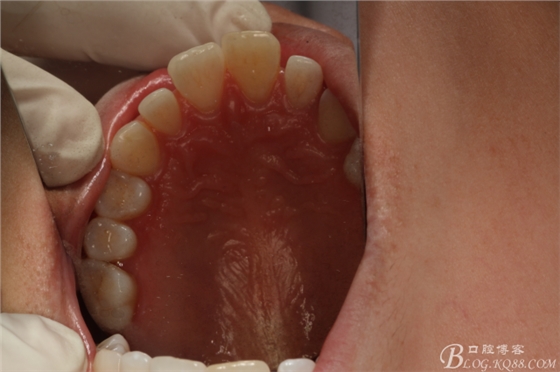

圖2.腭側(cè)口內(nèi)像觀:腭側(cè)平坦,未捫及隆起